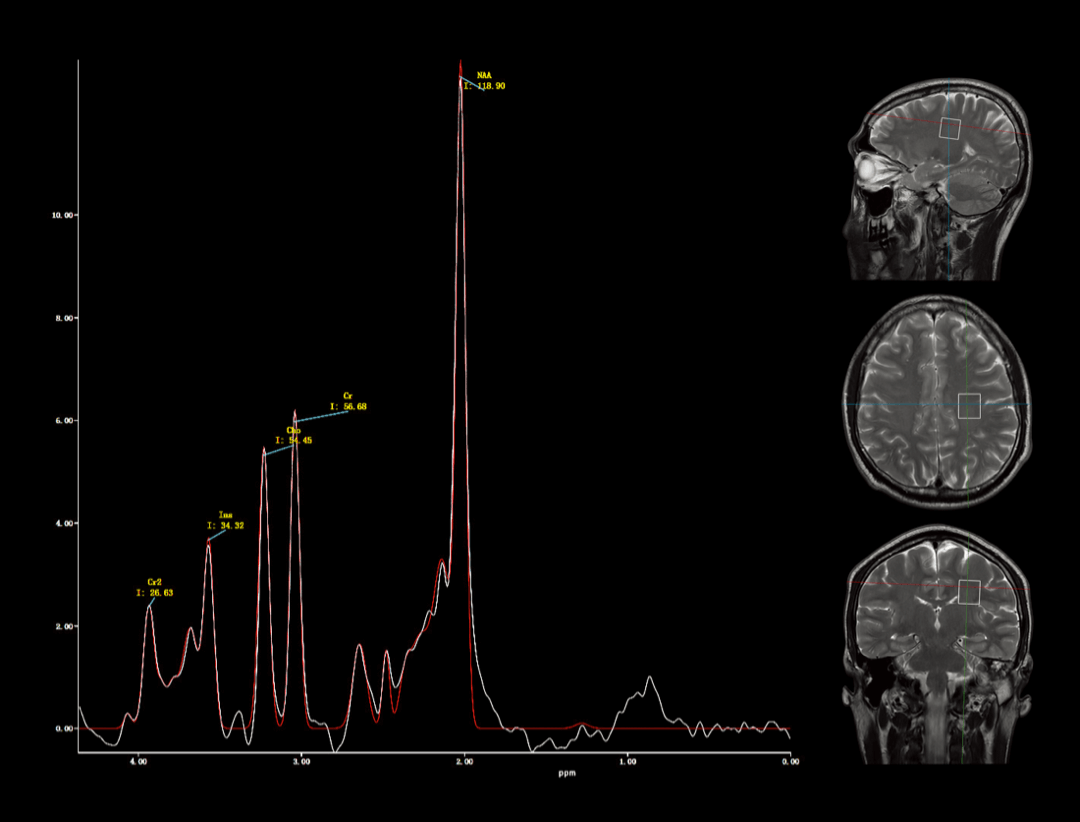

波谱成像

用于研究人体内代谢含量分析,完成活体组织代谢物水平的无创检测。